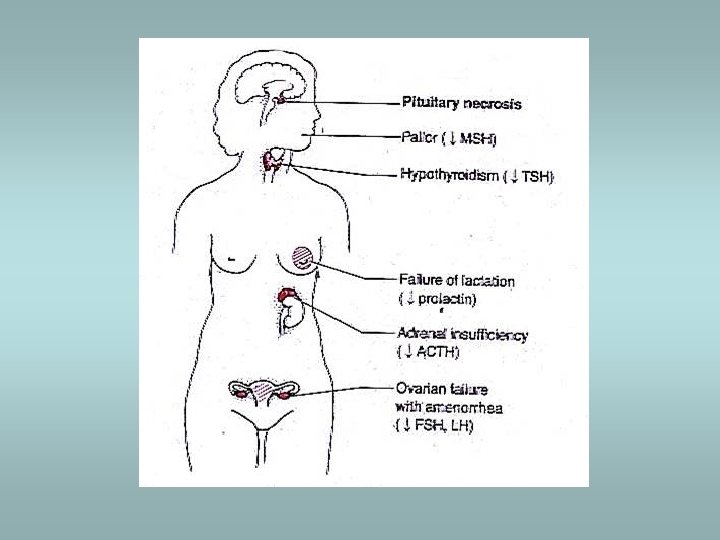

Hypopituarism Caused by 1) hypothalamic lesions: ü Craniopharyngioma ü Glioma ü Germinoma 2) pituitary lesions: ü Nonsecretory adenomas ü Sheehan’s syndrome ü Empty sella syndrome Clinically – variable ü Hypogonadotropism ü Hypothyroidism, etc.

Sheehan’s syndrome ü ü ü Associated with obstetric haemorrhage or shock Caused by infarction of anterior pituitary Gonadal failure – inability to lactate ACTH, TSH deficiency Healing of necrosis – fibrous tissue